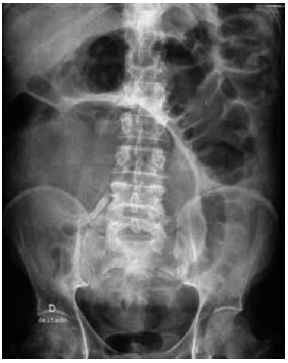

Homem, 70 anos, apresenta tumor no cólon esquerdo e está fazendo exames de estadiamento e avaliação pré-operatória. O exame de colonoscopia completo não revelou lesões sincrônicas. Aguardando ser novamente atendido, começou a apresentar dor abdominal e distensão importante do abdome, com parada de eliminação de gases e fezes. Procurou o pronto-socorro, sendo que lhe foi solicitada uma radiografia do abdome (VIDE IMAGEM).

Após avaliação, a equipe cirúrgica deverá indicar ao paciente